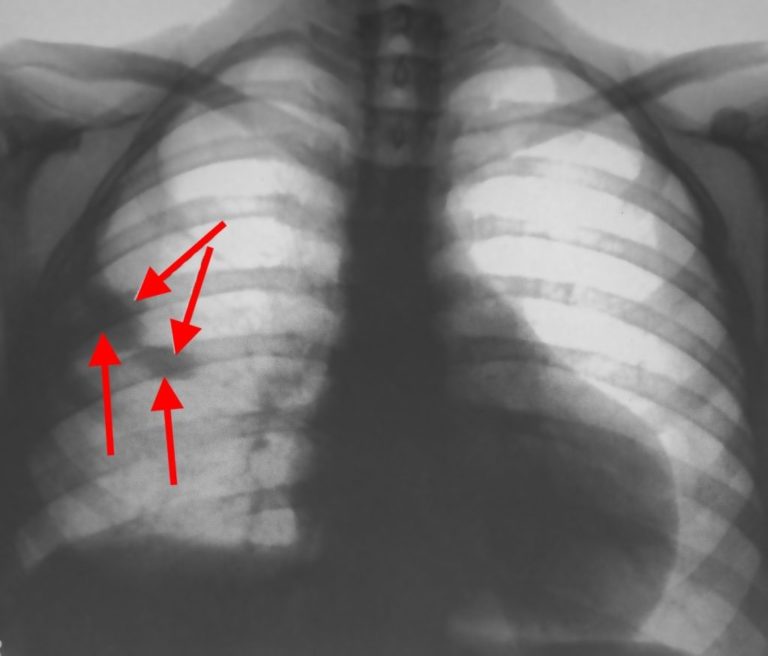

Рентген легких

Не реже одного раза в год необходимо проходить рентгенографию легких. Это современное медицинское исследование позволяет выявить начальные признаки заболеваний бронхо-легочной системы на ранних стадиях.

С помощью рентгеновского аппарата можно обнаружить:

- отклонение одного из куполов легких при поражении одной из сторон;

- деформацию правого предсердия и желудочка;

- увеличение сосудистой системы в области корней легких;

- расширение ветви легочного ствола (нисходящей артерии);

- сужение сосудистой сети на клеточном уровне;

- спадение доли легкого;

- тень, напоминающую треугольник с вершиной, направленной внутрь легочной системы;

- наличие жидкости в легочных тканях.